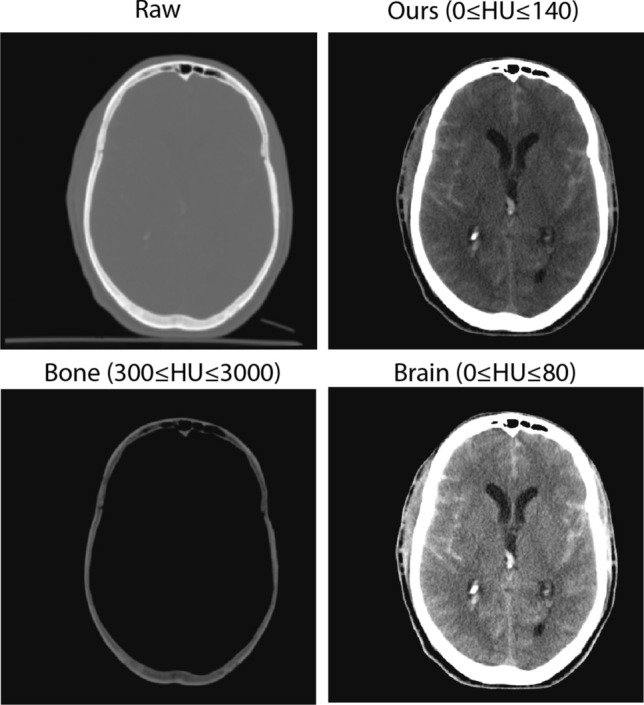

Hematoma segmentation in traumatic brain injury (TBI) is critical for accurate diagnosis and effective treatment planning. In this study, we evaluate various automated segmentation models, including stat-of-the-art architecture as benchmarks, and compare their performance with our proposed SAM-Adapter method for segmenting hematomas in brain CT scans. By incorporating the adapter into the vanilla SAM model, we address the challenges in medical imaging, which has very limited annotated datasets, enhancing model performance efficiency. We also find that domain-specific pre-processing, such as contrast adjustment, reduces the need for extensive pretraining, making the model more streamlined. And the model performance benefited with optimization and hyperparameter tuning. Our results demonstrate that the SAM-Adapter model achieved strong performance and reliability in identifying hematomas with Dice (72.34%), IoU (59.78%), 95% HD (5.57), sensitivity (75.39%) and specificity (99.73%). Inter-observer variability was assessed, revealing that the model's performance Dice (67.20%) was closely aligned with human expert agreement Dice (63.79%), suggesting its potential clinical utility. The external validation on the HemSeg-200 dataset, which contains 222 scans, demonstrates the robustness of our approach across diverse cases. These advancements in automatic segmentation hold promise for improving the accuracy and efficiency of TBI diagnosis, supporting clinical decision-making, and enhancing patient outcomes.